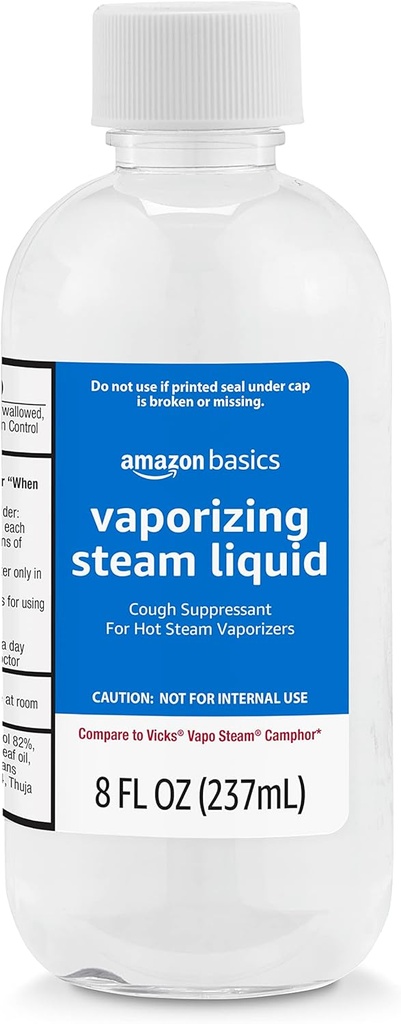

基礎蒸気液体の咳の抑制剤の薬物、8 Fl Oz (前例:Solimo)のパック

- 浸透させた蒸気液体の咳の抑制剤の8-fluidのオンス ボトル

- 熱い蒸気の蒸発器だけのため。 口から取らない

- 風邪に関連した咳を緩和

購入基本蒸気液体咳抑制薬、8 Fl Oz(前例:ソリモ) ✓ 資格のある注文で送料無料

| 原料: | ディメチコン, メンソール, リース-7, ユーカリ グロブラス リーフ オイル, 活動的な: Camphor 6.2% 活動的な: アルコール 82%, Myristica Fragrans (nutmeg) カーネルオイル, ポロキシマー 124, トゥジャ |

| 有効期限 | 9月2027日 |

| 項目 次元 L X W X H | 2.4 x 2.4 x 6.52インチ |

| ブランド | Amazonの基本 |